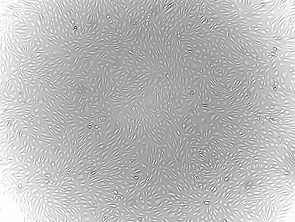

Product Image

Human Extrahepatic Bile Duct Epithelial Cells are isolated from normal human bile duct tissue. Each vial contains >5 x 105 cells in 1 ml volume.